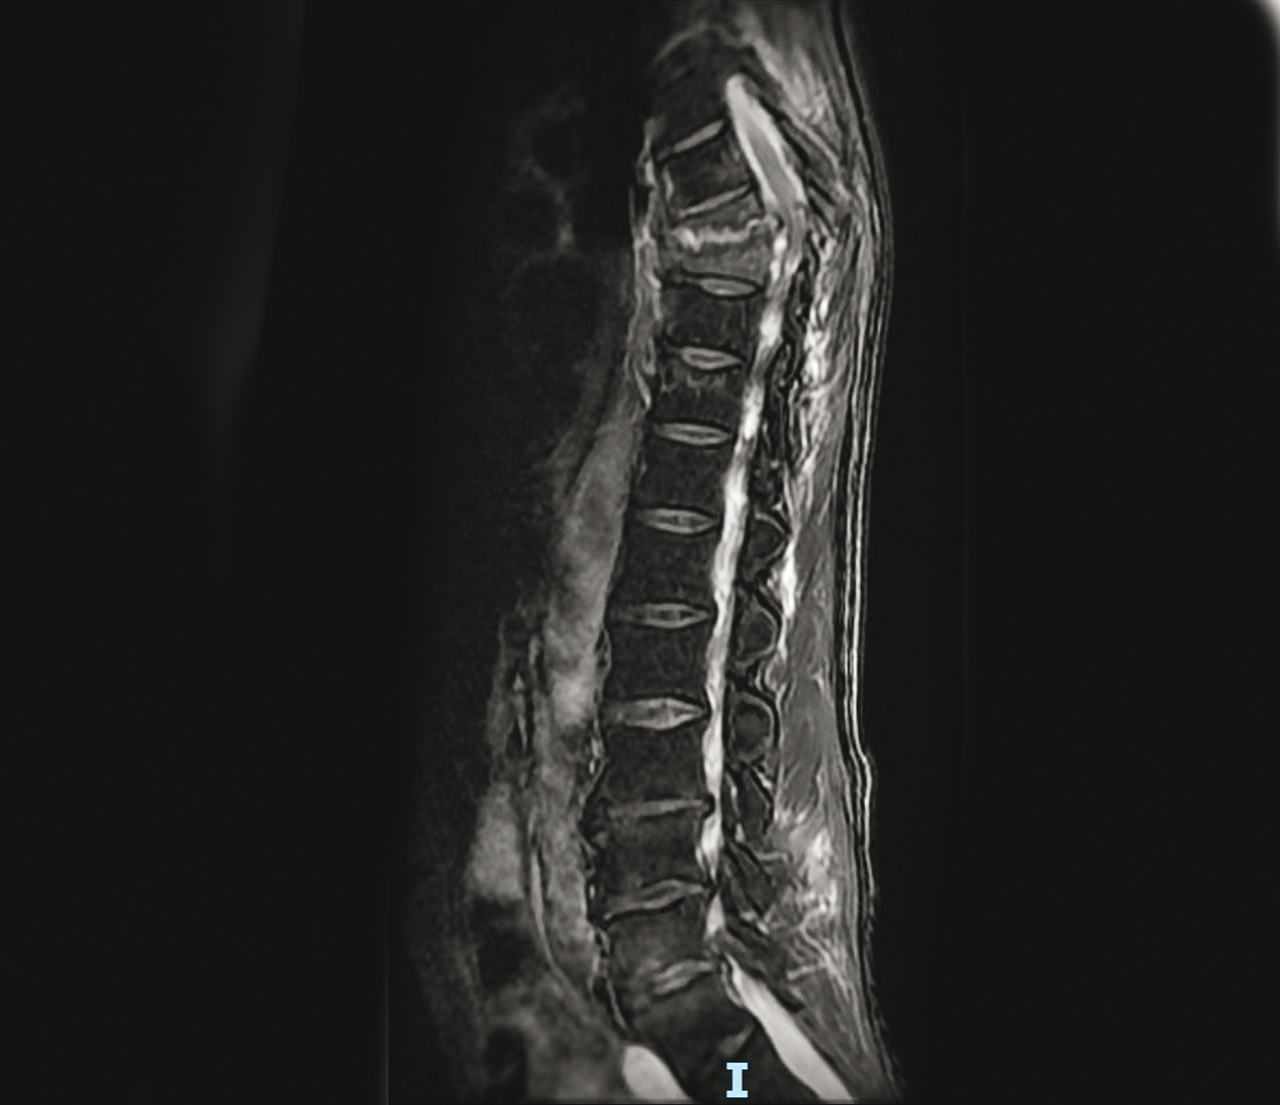

Homme de 60 ans se plaignant de dorsalgies depuis 2 mois, avec altération de l’état général et CRP est à 40 mg/L.

Quel est votre diagnostic ?